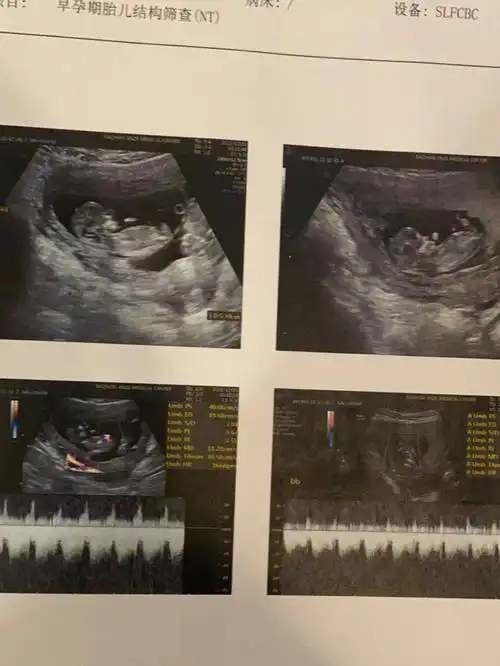

孕3月男女胎儿个性藏得深,摸清b超这几个数据,胎儿就没啥秘密了

12周nt男宝特点nt值是什么nub点看男女准不准

nt12周看见小丁丁了很神奇很准的nt看男女方法

双胎nt看男女

12周nt能看出男女吗